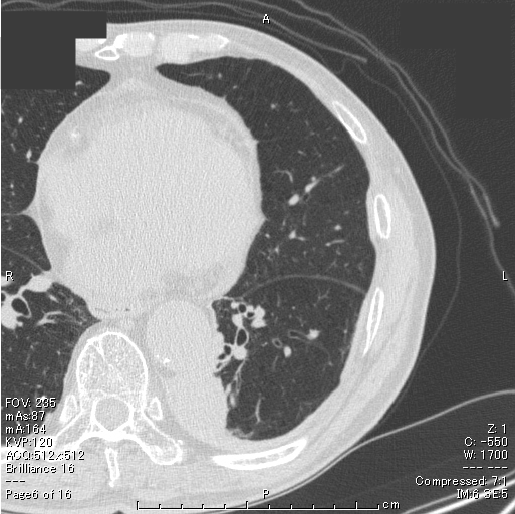

円形無気肺 胸部画像

胸部単純CT(肺野条件)では、左肺S6の椎体に接する部分に腫瘤影を認め、円形無気肺に特徴的なcomet tail signを認め、円形無気肺と診断した。